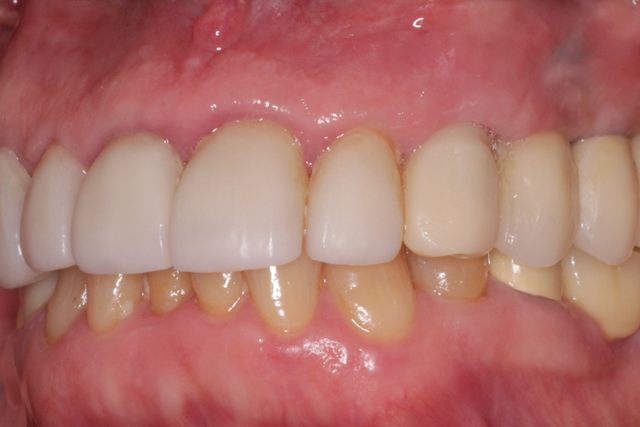

This technique utilizes a digital workflow to provide initial implant planning, placement and esthetic sculpting of the gingival tissues. It affords the ability to start contouring an ideal emergence profile at the time of implant placement (Fig. 11).

Fig. 11

The provisional crown will be in place for three months and, following Ostell testing again, a final restoration affording optimum tissue contour will be fabricated.